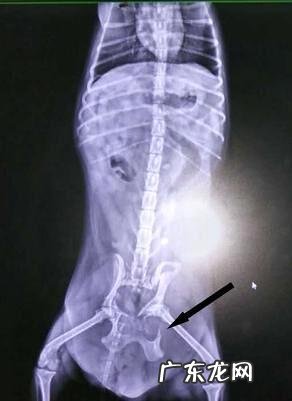

X光影像诊断确诊:逆位和侧方评定盆骨的损害,显示信息骨裂面,膀光X光片和尿道口造影检查显示信息是否尿道口和膀光损害 。

文章插图

流浪犬髂骨骨裂,箭头符号所显示为骨裂处 。